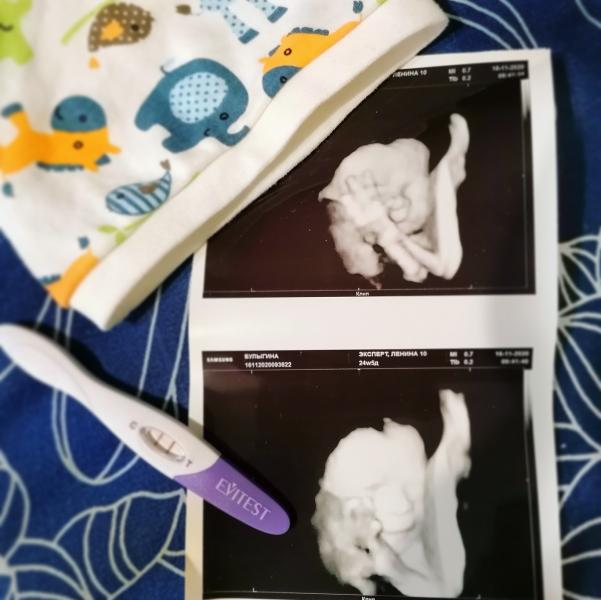

Наш Дар - наша дюймовочка.

Сегодня поехала на УЗИ чтобы проверить, что за образование на плаценте, в итоге ничего страшного в нем нет, такая особенность в общем у нас, влияния на плод не должно.

Дариночка у нас все же кнопочка растёт (вес 617г) , ждать, что будет хомячок в 4 кг не стоит 😃 что тоже хорошо, в принципе и Марианна не была крупной. Развитие все по сроку, все хорошо, это главное. Кровотоки маточные, в пуповинке тоже нормально. Сердцебиение 146 ударов💪